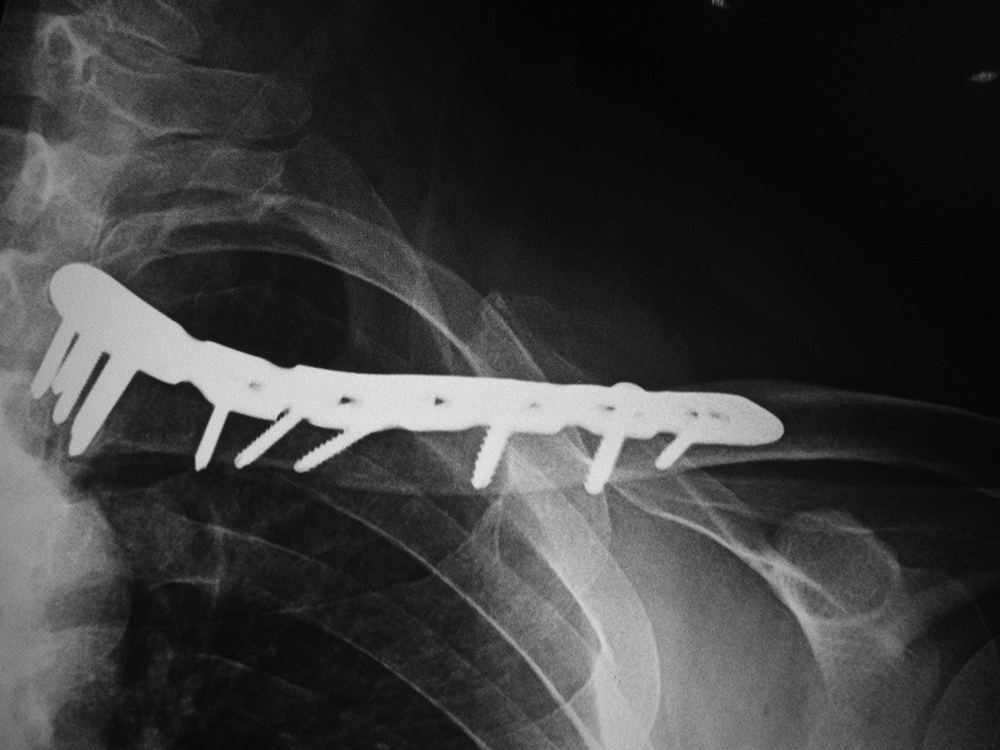

Right clavicle reconstruction plate

Left clavicle reconstruction plate

Clavicle reconstruction plate

67 year-old man with healing left proximal clavicular fracture.